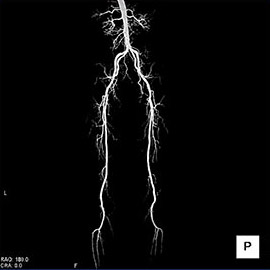

80列マルチスライスCTで撮影した画像

心臓(冠動脈)

主に狭心症や心筋梗塞などの診断